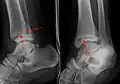

![]() | |

| Fracture of both sides of the ankle with dislocation as seen on anteroposterior X-ray. (1) fibula, (2) tibia, (arrow) medial malleolus, (arrowhead) lateral malleolus | |